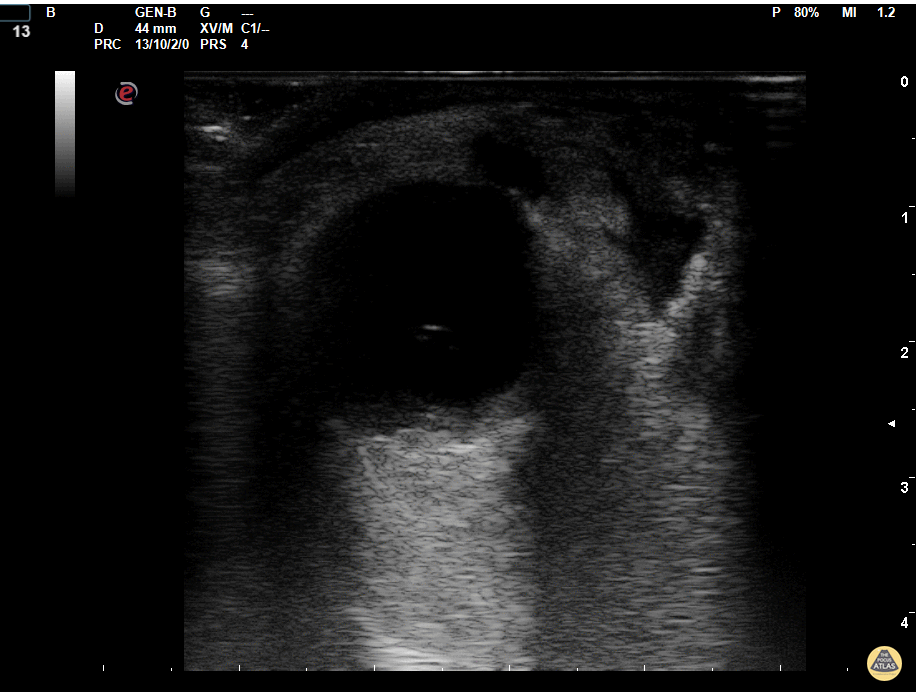

Orbital cellulitis evolving into abscess in diabetic patient. Multiple pus collections are visible on the medial side. Dr. Marco Garrone